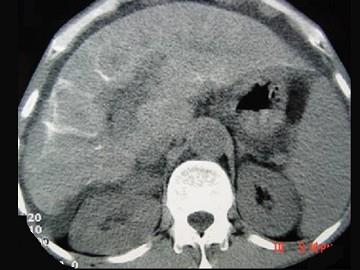

问题 男性,63岁,腹胀、双下肢水肿、乏力、食欲不振,影像所见如下图,最佳的诊断是 ( )

选项 A.酒精性肝硬化 B.血吸虫肝硬化 C.肝炎后肝硬化 D.局限性脂肪肝 E.原发性肝癌

答案 B